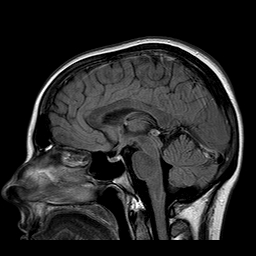

Демиелинизирующие заболевания мозга: МРТ изображения